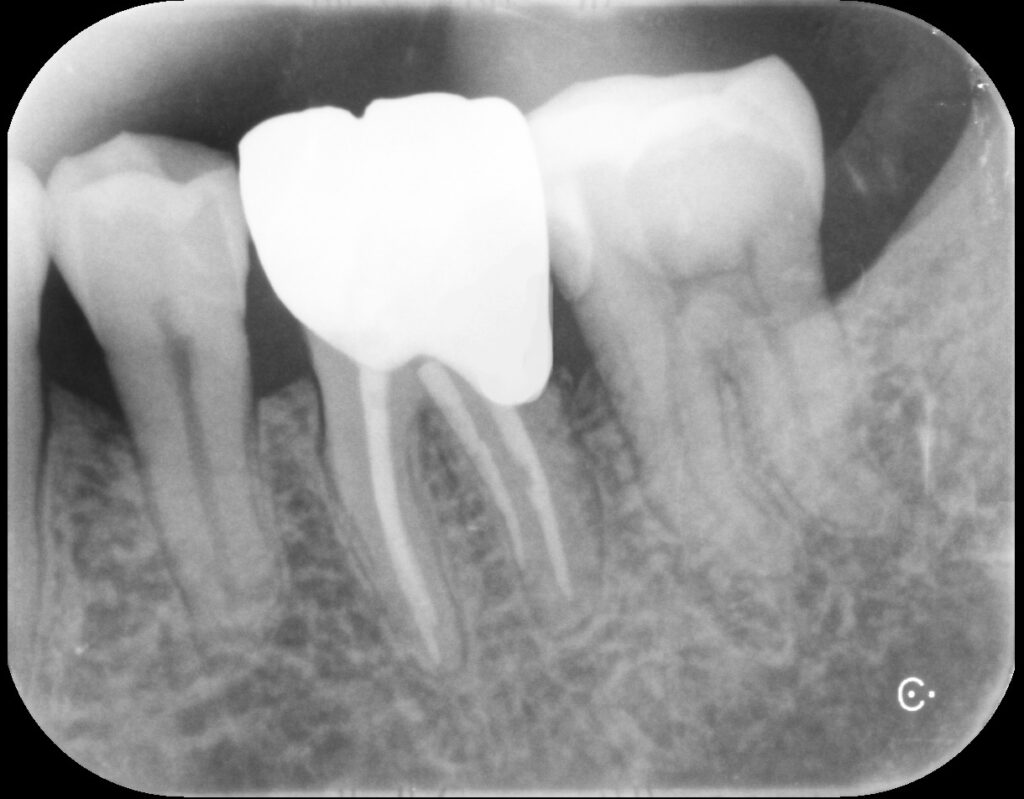

최종 수복 | 크라운(치과 보철) 완료

신경치료 후, 치아 구조가 약해진 어금니를 보호하기 위해 크라운(crown, 치과 보철물) 을 제작·장착했습니다.

신경치료를 마친 치아는 내부 수분과 영양 공급이 차단되어 파절(부러질) 위험이 높아집니다. 크라운은 치아 전체를 감싸 이런 위험을 방지하고, 정상적인 저작 기능을 회복시켜줍니다.

치료 결과, 환자분은 불편 없이 정상적인 교합과 기능을 회복하셨습니다.